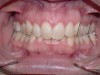

If the maxillary anterior teeth are positioned or inclined palatally, upon closure the lower teeth are going to first contact these teeth, which will force the mandible to shift to close into a retruded position. The objective is to try to identify this shift from primary contact to closure. This type of fence could potentially lead to shifting of the maxillary anterior teeth, breaking of the teeth, and/or muscular and jaw dysfunction as a result of posterior displacement of the mandible (Figures 2 through 5).

Figure 2

Figure 3

Figure 4

Figure 5